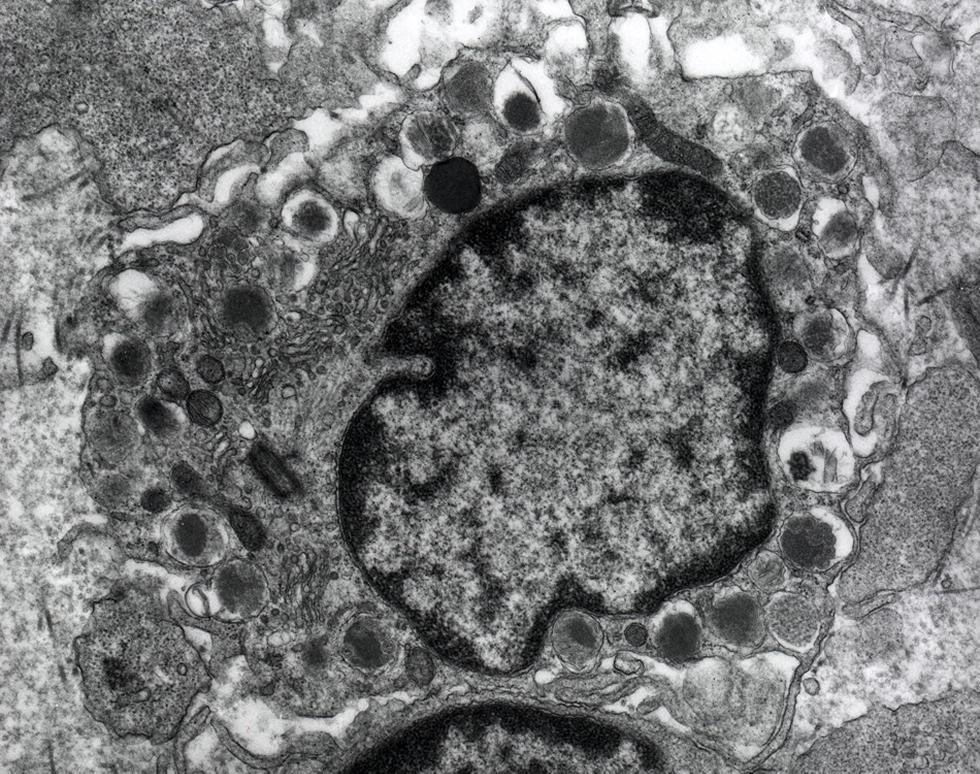

Mast cell